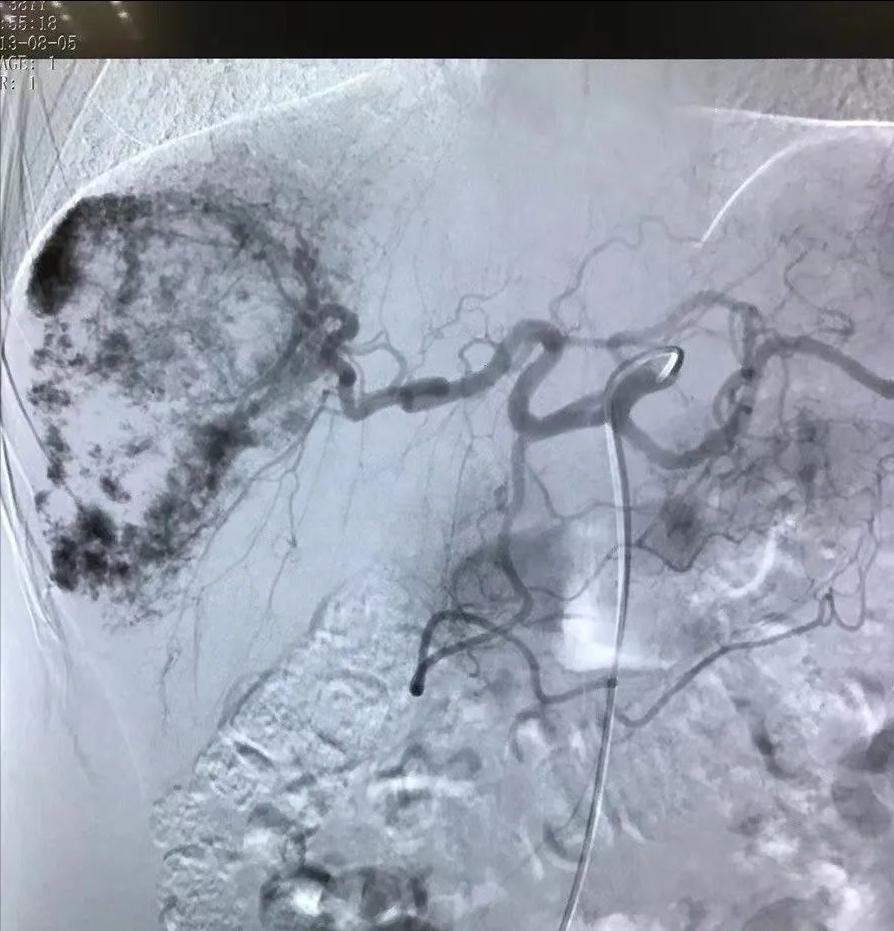

外周血管介入是介入治疗的一大分支 ,是指在医学影像设备引导下,经血管穿刺途径对 除颅内血管和心脏冠状血管以外的其他血管 进行诊断或者治疗的技术,不包括经血管途径对肿瘤性疾病进行诊断或者治疗的技术。

介入治疗的一大分支是外周血管介入,是指在医学影像设备引导下,经血管穿刺途径对除颅内血管和心脏冠状血管以外的其他血管进行诊断或者治疗的技术,不包括经血管途径对肿瘤性疾病进行诊断或者治疗的技术。

目前,我国周围血管疾病的介入治疗在临床中的应用也日趋广泛。介入治疗具有简便安全、微创伤性、合并症少、定位准确、可重复性等优点。外周血管疾病的介入治疗的范围已从原来的肢体动脉发展到大动脉以及静脉,甚至全身几乎所有的血管。目前最为成功的是髂、股动脉、肾动脉和下腔静脉狭窄的介入治疗。介入治疗的范围主要是血管狭窄或闭塞、血管扩张及血管畸形三大类疾病。

目前外周血管疾病的介入治疗方法主要有球囊血管成形术及血管支架置入术。球囊血管成形术的最佳适应证是中等大小或大血管局限、孤立性短段狭窄,其次为多发、分散的短段狭窄和闭塞。长段狭窄或闭塞、小血管病变、溃疡性狭窄或已有钙化的狭窄或闭塞病变不适宜于PTA治疗。血管支架是指在管腔球囊扩张成形的基础上,在病变段置入内支架以达到支撑狭窄闭塞段血管,减少血管弹性回缩及再塑形,保持管腔血流通畅的目的。部分内支架还具有预防再狭窄的作用。另外,动静脉血栓形成可行介入导管血栓清除术及留置导管接触性溶栓治疗,相对于外科手术,风险小,并发症少,患者耐受性强,相对内科药物治疗效果好。动脉瘤的治疗,选用覆膜支架隔绝瘤体进行局部腔内血管成形术,同时能保持血管管腔通畅,大大降低了动脉瘤破裂出血的风险。